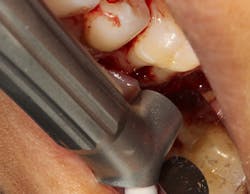

Figure 2: Solea laser with a beam size of .5 mm used to detoxify furcation. This beam can penetrate deep into the furcation.

The advent of laser technology, either as an adjunct to surgical therapy or as a monotherapy, has been met with mixed results in the literature.13 Recently, a new 9.3-micron CO2 laser (Solea from Convergent Dental) with the ability to cut both hard and soft tissue with efficiency was introduced to the dental market. This laser can penetrate deep defects with enough power to both thoroughly detoxify root surfaces and remove fibrous tissue, enhancing tissue repair (figure 2).14 The spot size of the focal laser beam can also be controlled to a range of .25 mm to 1.25 mm so that the beam can be directed into furcation entrances. This allows previously difficult furcal defects to be detoxified prior to regenerative therapy. Because of this enhanced ability to detoxify, this laser has been able to change the prognosis of once-hopeless teeth (figure 3) and allow for tissue regeneration (figure 4) instead of extraction.